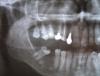

Balug Опубликовано 5 марта, 2011 Поделиться Опубликовано 5 марта, 2011 Здравствуйте, уважаемые стоматологи.Прошу вашей консультации, так как случай непростой (на 5 разных консультациях получил 4 разных рекомендации ).Верхние 2 и 4 находятся под коронкой 5-7 лет, приблизительно раз в год (зимой) вызывали некоторое беспокойство – побаливали, но полоскание содой и ромашкой боль снимали. Однако в этом году боль почти сразу стала очень сильной, полоскания не помогали.При обращении в поликлинику сделали локальный снимок и на его основании сказали, что причина в 3 зубе, его рассверлили, удалили нерв (как потом выяснилось не до конца), однако боль не проходила и на следующий день образовался флюс. При обращении в другую поликлинику сделали панорамный снимок и сказали, что 3 не при чем, а киста на 4 заходящая за 3 до 2. Для уточнения диагноза сделал КТ. Далее прочистили до конца 3 (для чего часть зуба спилили, он оказался очень длинным) и запломбировали его временной пломбой. Сделали надрез и дренаж. После чего лечение антибиотиками (аугментин 500мг/125мг), полоскание. Опухлость спала, боль прошла.Основной вопрос, что делать дальше?При консультации разных специалистов были следующие основные рекомендации: 1. Удалить 2 и 4, почистить полость и далее имплантация, либо имплантация и мост. 2. Удалить 4, почистить и мост. 3. Зубы не удалять, почистить полость и свободную область заполнить Изиграфтом. Что делать, какие из рекомендаций реальные? Конечно, вариант 3 мне нравится больше всего, все-таки все свои зубы остаются, но посмотрел по интернету отзывы об Изиграфте не супер. Да и не будет ли рецидивов? Возможна ли полная чистка в моем варианте? Кстати, при удалении зубов, полости все равно надо будет чем-то заполнять? Чем? Хотелось бы услышать Ваши предложения.Прилагаю снимок и КТ Yuriy Gennadievich Ссылка на комментарий

Bier Опубликовано 7 марта, 2011 Поделиться Опубликовано 7 марта, 2011 3й вариант вообще не подходит никак. я толком не могу рассмотреть ваш снимок, лучше бы сделать прицельный этих 3х зубов на компьютере и выложить сюда сразу файл. либо перелечить проблемные зубы, либо удалить. сейчас вроде масса клиник, работающих по выходным в том числе. Ссылка на комментарий

ПалСаныч Опубликовано 8 марта, 2011 Поделиться Опубликовано 8 марта, 2011 Скачал Ваше КТ. К сожалению в прилагаемой программе для просмотра КТ нет фукнции менять плоскость среза, только предустановленные 3 плоскости. Что я мог заподозрить, то это то, что есть перфорация между корней 4 зуба, откуда и возникла киста распространяющаяся на клык и т.д. Сегодня вечером или завтра ,когда буду дома выложу те срезы Вашего КТ, на которых можно что то увидеть, что бы остальные коллеги тоже понимали о чем речь. Ссылка на комментарий